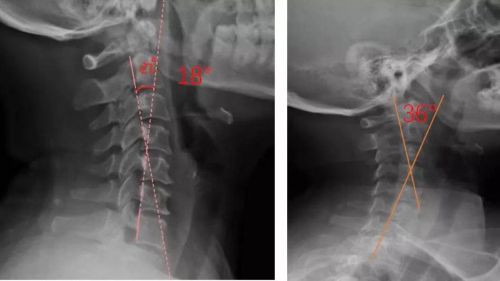

患者適配前后側(cè)位X光,佩戴前18°,適配后36°

對于頸椎病患者,合理設計的頸椎枕,能夠緊密適合頸椎,矯正頸椎生理曲度;再根據(jù)頸椎曲度改善情況,隨時間慢慢調(diào)整3D打印頸椎枕曲度,使變直的頸椎逐漸形成正常的生理曲度,改善頸肩痛的癥狀。